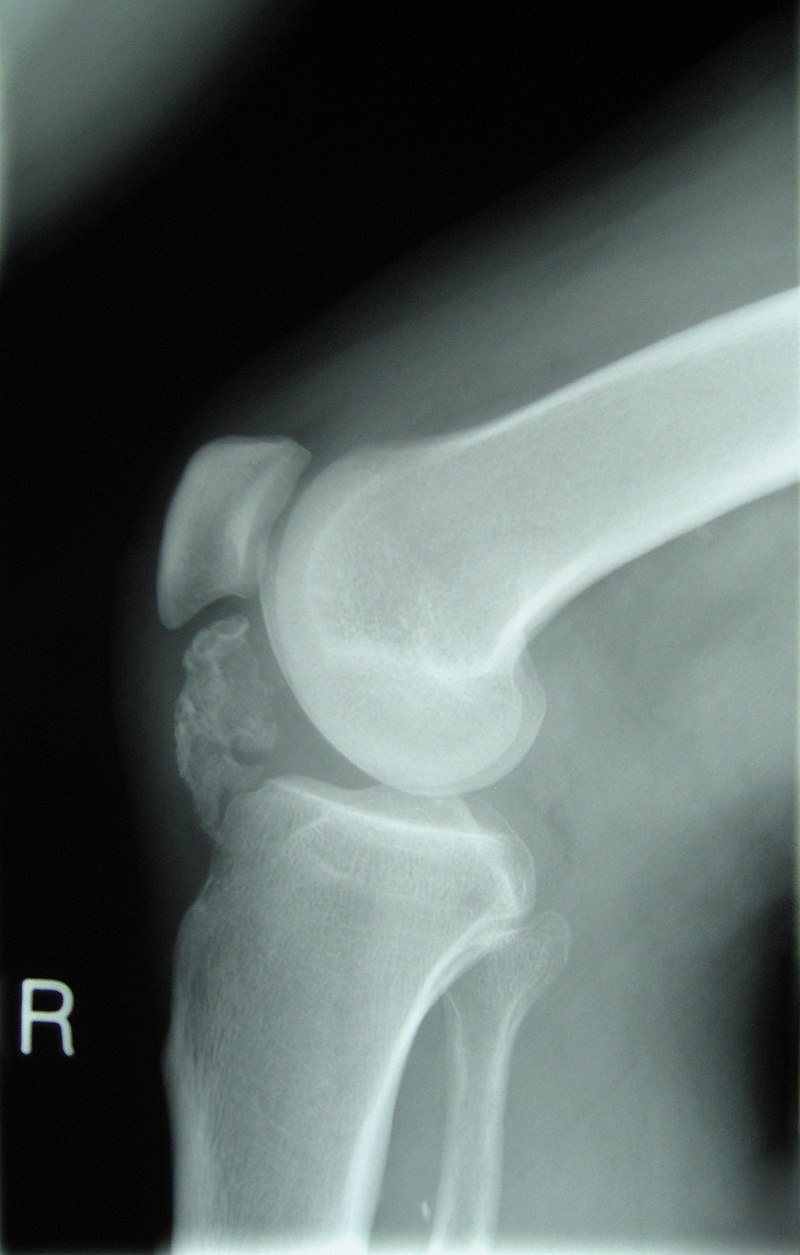

Giant Cell Tumor of the Bone

Giant cell tumor of the bone is composed of multinucleated giant cells and stromal cells that occur in young adults.

Giant cell tumor of the bone typically arises in the epiphysis of long bones, usually the distal femur or proximal tibia.

Radiology of giant cell tumor of the bone classically shows a “soap-bubble” appearance on x-ray.

Giant cell tumors of the bone are locally aggressive, and they may recur after surgical removal.